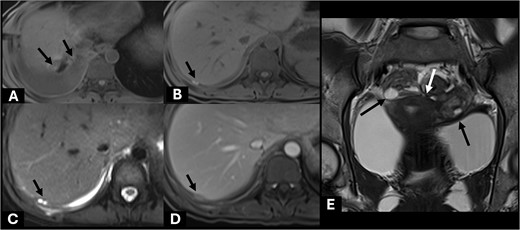

The patient was admitted for intravenous hydration, antibiotics, and close monitoring. Magnetic resonance cholangiopancreatography (MRCP) confirmed a normal appearance of biliary system without bile leakage or fistula. However, few subperitoneal nodules compatible with endometriotic implant nodules were noted (Fig. 4). No major biliary leakage was identified byendoscopic retrograde cholangiopancreatography (ERCP), however, a plastic stent was placed to decompress biliary tract. Further history taking revealed progressive dysmenorrhea over the past year, which was much worsening by expanding from suprapubic area to entire abdomen.

Axial precontrast T1W images (A, B) showed few subhepatic nodules (short black arrow) demonstrating hyperintensity, which measured up to 15 mm abutting posterior right hepatic capsule. It showed hyperintensity on T2W (C) and homogeneous enhancement on post contrast enhanced MRI (D). These findings are suggestive of endometriotic implant nodules with subacute hemorrhagic foci (short black arrow). Included MR pelvis on coronal T2W image (E) showed complex cystic lesions at both adnexae (long black arrow) with adjacent fibrosis (white arrow) creating kissing ovary sign appearance. These findings are compatible with pelvic DIE.

In this case, many evidences supported bilothorax was caused by “diaphragmatic endometriosis,” endometrial tissue implanting on the diaphragm. Diaphragmatic endometriosis was first mentioned by Brews A in 1954. Besides pelvic pain due to coexisting pelvic endometriosis, diaphragmatic endometriosis produces cyclic upper abdominal pain, shoulder pain and even chest pain [10]. The hyperintensity nodules would be demonstrated on fat-suppressed T1-weighted magnetic resonance imaging (MRI). The endometriosis located on diaphragmatic surface can infiltrate and penetrate through the thickness of diaphragmatic muscle, then result in pleuro-peritoneal connection or even thoracic endometriosis [11].